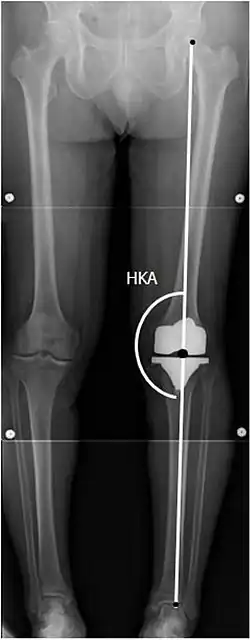

To indicate knee replacement in case of osteoarthritis, its radiographic classification and severity of symptoms both should be substantial. Such radiography should consist of weightbearing X-rays of both knees: AP, lateral, and 30 degrees of flexion. AP and lateral views may not show joint space narrowing, but the 30-degree flexion view is most sensitive for narrowing. Full-length projections also are used in order to adjust the prosthesis to provide a neutral angle for the distal lower extremity. Two angles used for this purpose are:

- Hip-knee-ankle angle (HKA),[11] which is an angle between the femoral mechanical axis and the center of the ankle joint.[12] It is normally between 1.0° and 1.5° of varus in adults.[13]

Knee replacement is routinely evaluated by X-ray, including the following measures:

![HKA: Hip-knee-ankle angle, which is ideally between 3° varum to 3° valgum from a right angle.[62]](./_assets_/X-ray_of_HKA_angle_with_knee_prosthesis.jpg)

- FFC: frontal femoral component angle. It is typically regarded as optimal when being 2–7° in valgus.[63]

- FTC: frontal tibial component angle, which is regarded as optimal when being at a right angle. A varus position of more than 3° has generally been found to increase the failure rate of the prosthesis.[63] -

- LTC: lateral (or sagittal) tibial component angle, which is ideally positioned so that the tibia is 0–7° flexed compared to at a right angle with the tibial plate.[63]